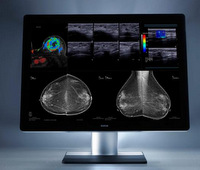

Coronis Uniti(MDMC-12133)は、最新の1,200万画素、常用1,000cd㎡の高精細・高輝度専用液晶パネルによる飛躍的な画質の向上による読影ワークフローの統合と、読影快適性の改善による高い生産性を目指して開発されたバルコのフラッグシップモデルである。本製品はマンモグラフィ・トモシンセシス診断用として米国FDA510Kを取得、本年4月のITEMにて国内販売が開始されたが、さらにこの度2015年8月10日付けにて、日本乳がん検診精度管理中央機構による適合モニタとして認定された。

1.最新の1,200万画素、常用1,000cd㎡の専用高画質液晶パネルとLEDバックライトを採用。多目的マルチモダリティカラー画像も、高精細マンモグラフィ画像も1台でより効率よく、より快適な画像診断環境を提供するオール・モダリティ医用画像表示ディスプレイである。